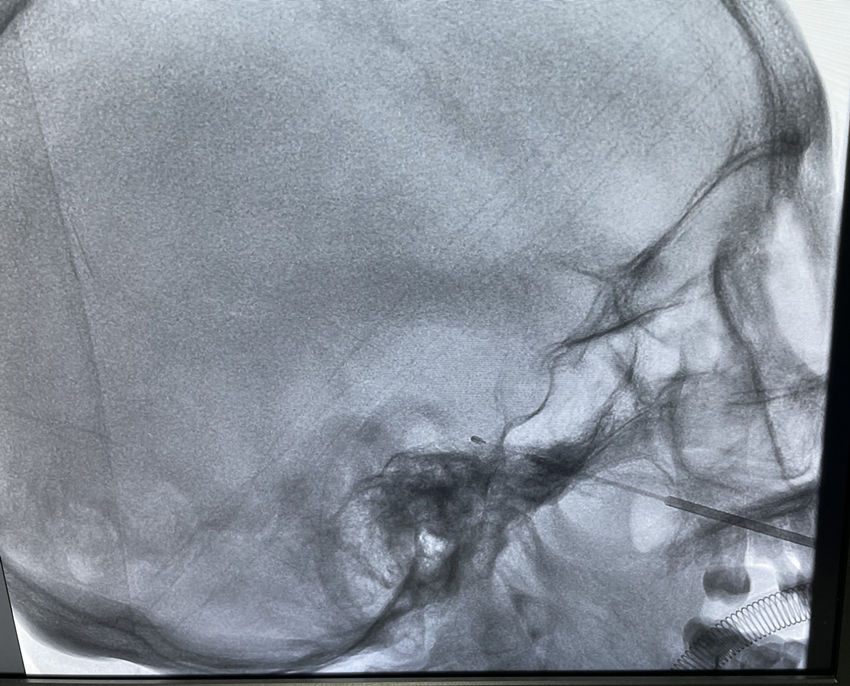

文章插图

▲穿刺针从患者右口角外的脸颊部位进入